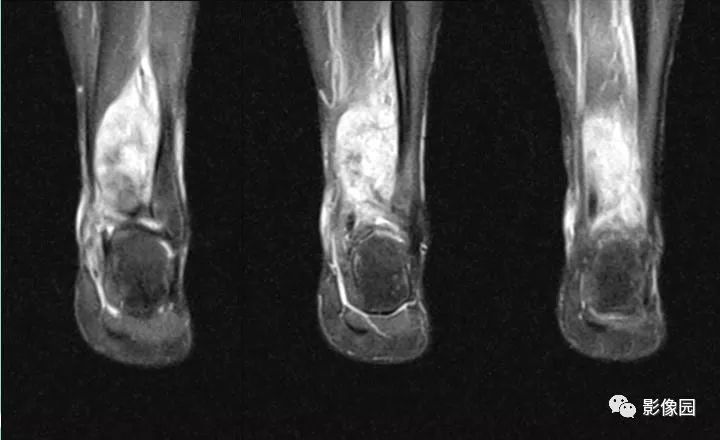

评论:前片X线示左胫骨下段及干骺端病变,髓腔内密度不均匀增高,内侧骨皮质可见骨质破坏,可见骨膜反应。CT示病灶内见多发斑片状肿瘤骨(黄色箭头),周围可见针状骨膜反应(红色箭头)。周围软组织肿胀。MRI示胫骨下段以长T1、长2信号为主的混杂信号影,未跨越胫距关节面,周围未见明显软组织肿块。周围软组织广泛片状长T1长T2信号影。复查X线示病变较前片明显进展,左侧胫骨远段及干骺端骨质破坏,周围可见针状骨膜反应及Codman三角(蓝色箭头)形成。相邻左侧腓骨下端、距骨滑车受累。